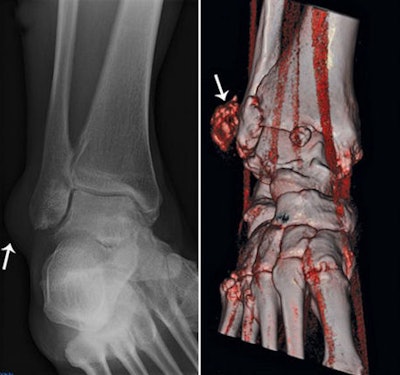

The second patient was a 45-year-old woman who presented to the emergency room with swelling along the right lateral malleolus but no history of trauma. Ultrasound depicted nonspecific soft-tissue swelling consistent with a mass or inflamed bursa, or potentially a soft-tissue sarcoma. Dual-energy CT confirmed that the mass was a tophus, a diagnosis confirmed by ultrasound-guided joint aspiration and mass aspiration.

![]() |

| A 45-year-old woman with swelling along lateral malleolus of right ankle but no history of trauma. Left, radiograph shows nonspecific soft-tissue swelling overlying lateral malleolus (arrow). Right, 3D volume-rendered coronal dual-energy CT image reveals that mass is composed of monosodium urate (red) consistent with tophus (arrow). |